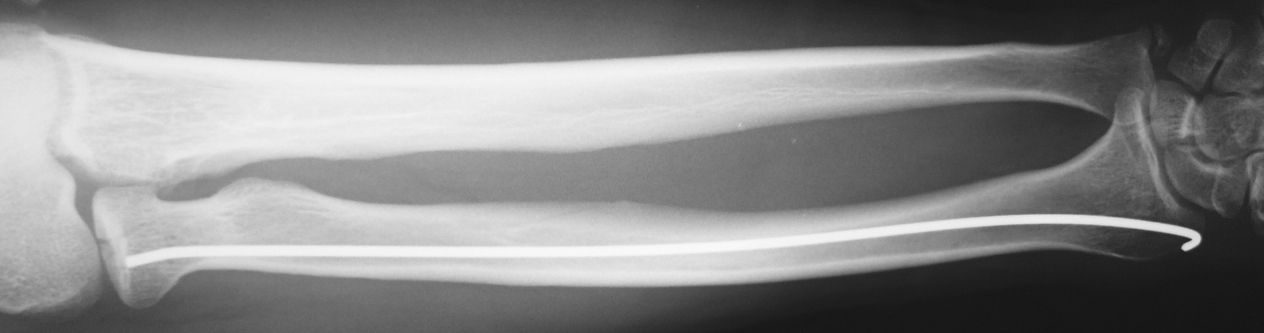

今日の午後は橈骨頭骨折の手術を行いました。単純X線像では分かりにくいのですが、CTを再構成した前額断像では関節面中央のみが陥没しているタイプの骨折でした。

比較的橈骨頚部の連続性は保たれていたので、橈骨頚部骨折と同様のK-wireを用いた整復・固定術を施行しました。今回使用したK-wireは2.0mmです。

まず、橈骨茎状突起先端の直上に約1cmの切開を加えて皮下を鈍的に剥離して橈骨茎状突起部を展開しました。橈骨神経浅枝損傷を避けるためにエアターニケットを使用します。

2.0 K-wireで皮質骨を開窓してから一旦抜去します。K-wireのお尻側の先が鈍な方を先頭にして、再度橈骨内に刺入します。この時にK-wireの先端を僅かに曲げておきます。

ハンマーで叩打しながら橈骨内を中枢方向に進めていきます。橈骨骨幹部を過ぎると急に抵抗が無くなり、あっという間に橈骨頚部に到達するので叩き過ぎに注意します。

橈骨頚部に到達した時点で、先ほど曲げたK-wire先端の方向を微調整します。橈骨茎状突起部のK-wireの断端は皮下に埋没しました。橈骨神経浅枝に接触しないように位置を調整します。

今日の手術も10分程度で終了しました。低侵襲なのに得られるメリットが大きいので良い手術だと思います。